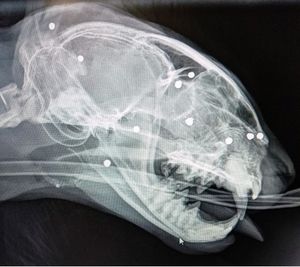

X-rays were performed and revealed numerous pellets scattered all over Oscar's body, including one in his nose which was affecting his ability to eat.

"We suspected that he might have a foreign body but were astonished to find on X-rays under anaesthetic that he had multiple pieces of lead shot in his body – 45 in all – including one apparently in his right nasal cavity.